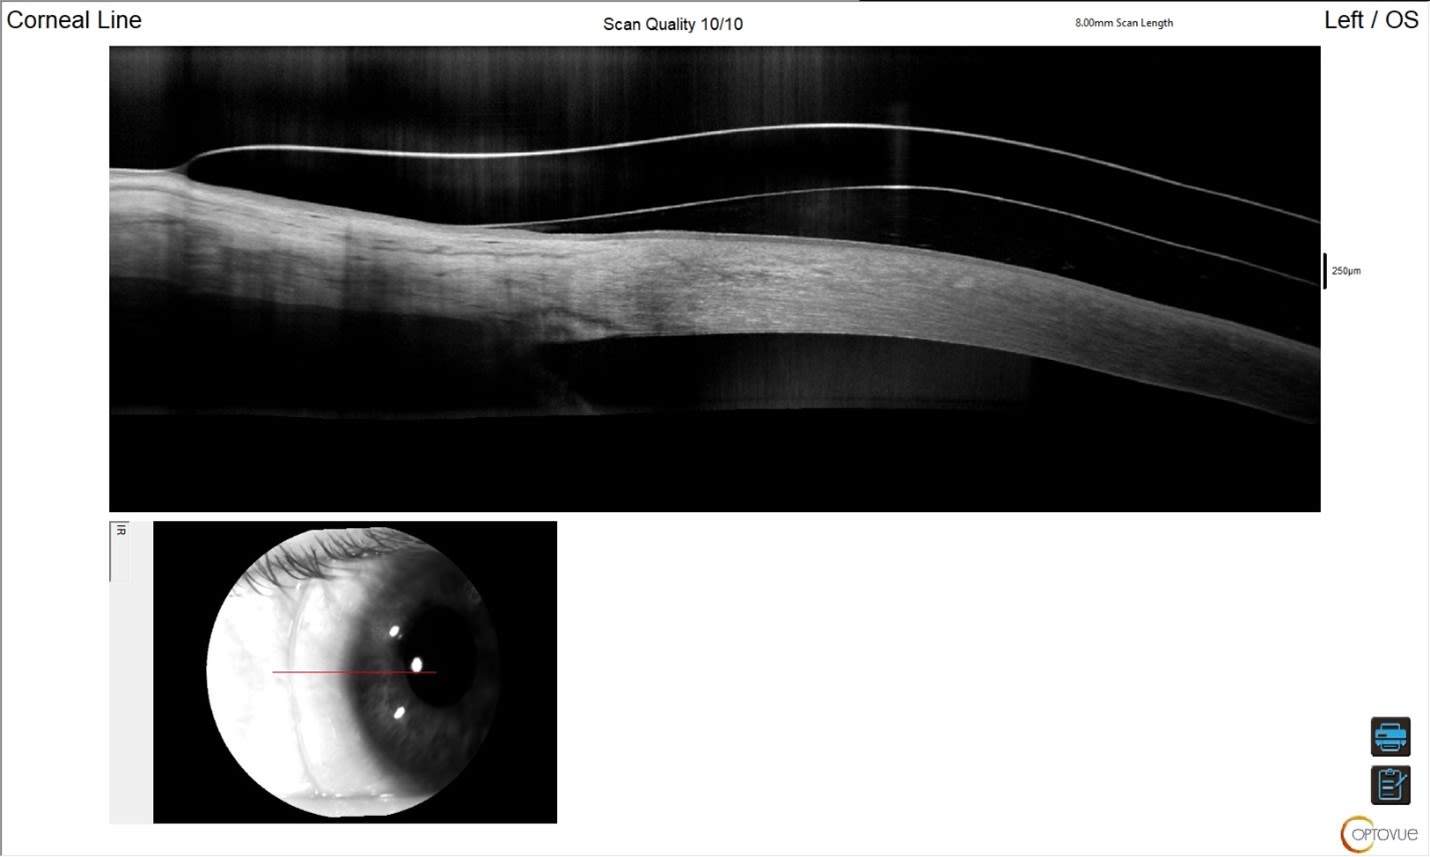

At dispense, AL’s vision was 20/20+2 OS. The anterior segment OCTs are shown below (Figures 2 through 6). We imaged scleral prosthetic lenses centrally and in four principal meridians at the haptics to ensure an optimal fit.

At the two-week visit, we noted that the limbal zone was tight (Figure 7), either due to forceful insertion (which creates a suction effect and pulls the lens onto the limbus) or standard settling of a prosthetic with spongy conjunctival tissue. We opted to educate the patient about gentle insertion technique and increased the optical zone diameter to allow for greater limbal clearance.

Lenses were dispensed with a larger optical zone diameter to preserve their overall diameter and to allow for greater limbal clearance nasally and temporally—where the cornea is widest after settling onto the eye (Figure 8).